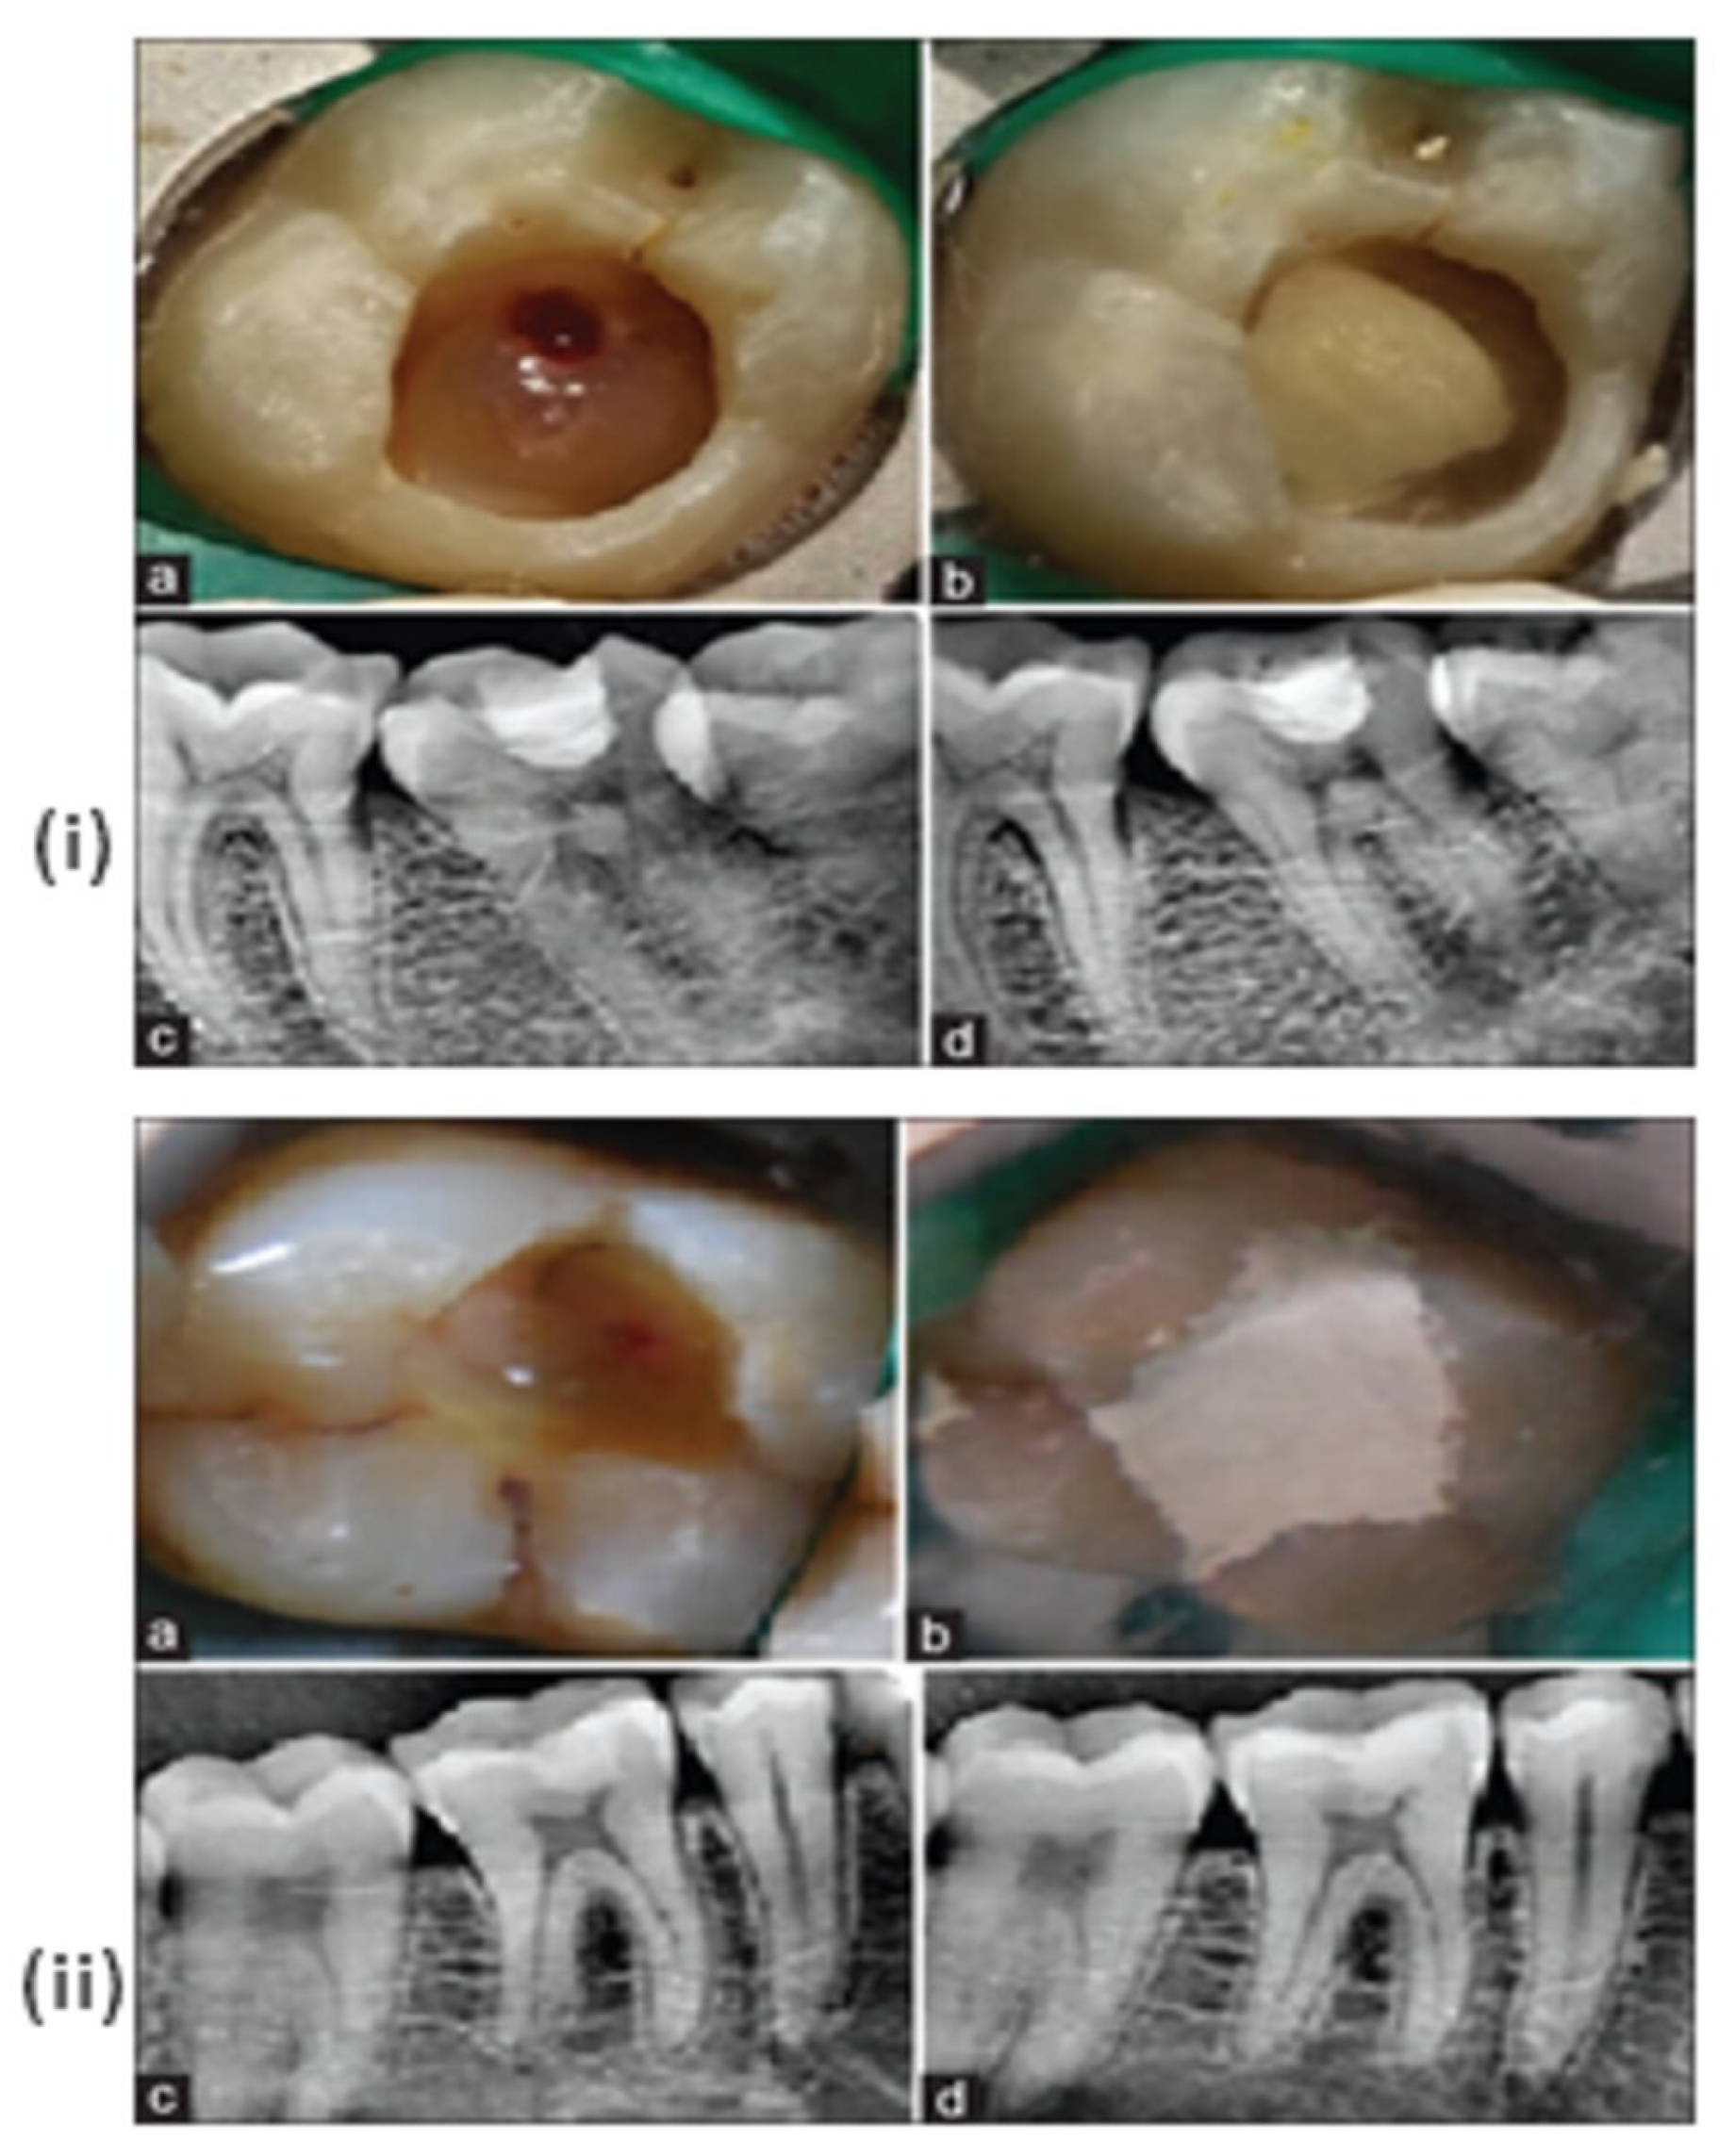

- Hegde, S.; Sowmya, B.; Mathew, S.; Bhandi, S.; Nagaraja, S.; Dinesh, K. Clinical evaluation of mineral trioxide aggregate and biodentine as direct pulp capping agents in carious teeth. J. Conserv. Dent. 2017, 20, 91–95. [Google Scholar] [CrossRef]

- Parirokh, M.; Torabinejad, M.; Dummer, P. Mineral trioxide aggregate and other bioactive endodontic cements: An updated overview—Part I: Vital pulp therapy. Int. Endod. J. 2018, 51, 177–205. [Google Scholar] [CrossRef] [PubMed]